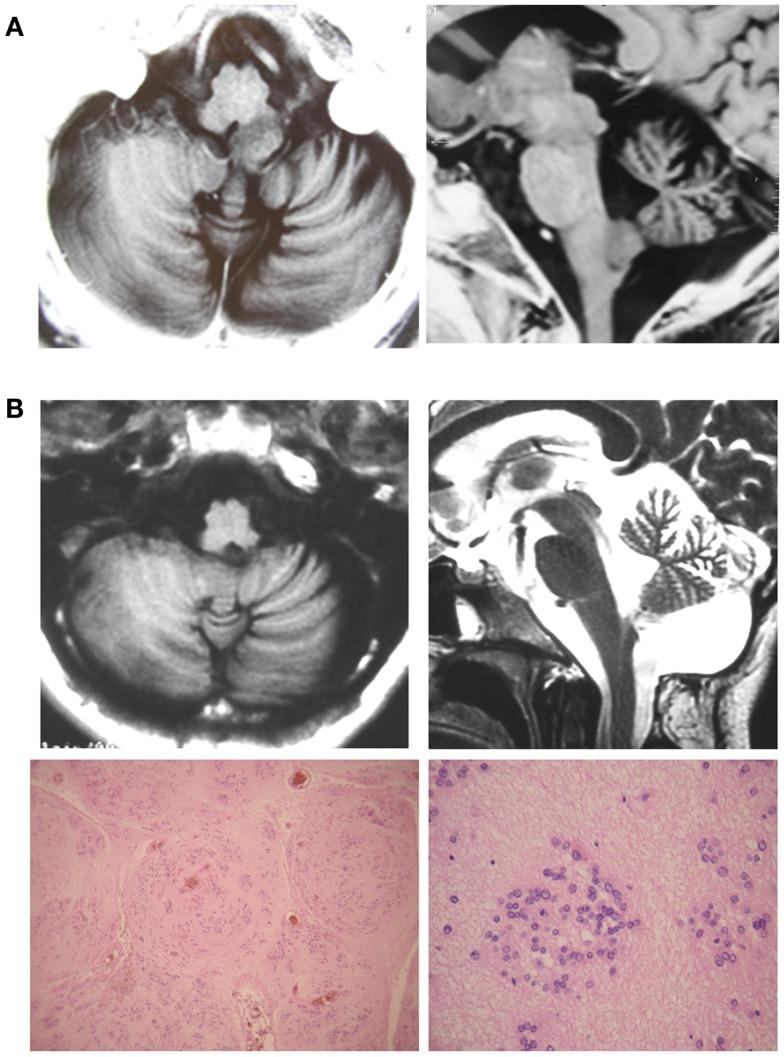

Medulla oblongata (MO) tumors are uncommon in adults. Controversies about their treatment arise regarding the need for histological diagnosis in this eloquent area of the brain, weighing benefits of a reliable diagnosis, and the potential disadvantages of invasive procedures. As a broader variety of pathological findings could be found in this localization, the accurate histopathological definition could not only allow an adequate therapy but also can prevent the disastrous consequences of empiric treatments. There are few publications about their surgical management and all belongs to small retrospective cohorts. In this scenario, we are reporting two patients with exophytic or focal lesions in the inferior half of the medulla, who underwent surgery by suboccipital midline subtonsillar approach. This approach was not specifically described to reach MO before, and we found that the lesions produced a mild elevation of the tonsils providing a wide surgical view from the medulla to the foramen of Luchska laterally, and up to the middle cerebellar peduncle, offering a wide and safe access.